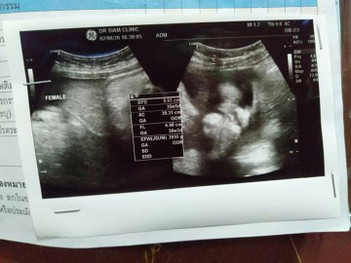

ผ่าคลอดก่อนกำหนด

วันนี้ไปหาหมอมาค่ะ น้องน้ำหนักเกินไป น้องหนัก 3930 กรัม หมอเลยแนะนำให้ผ่า เพราะตั้งใจทำหมันเลย ตอนนี้เรา 36+4 มีใครมีประสบการณ์ผ่าคลอดก่อนไหมค่ะ